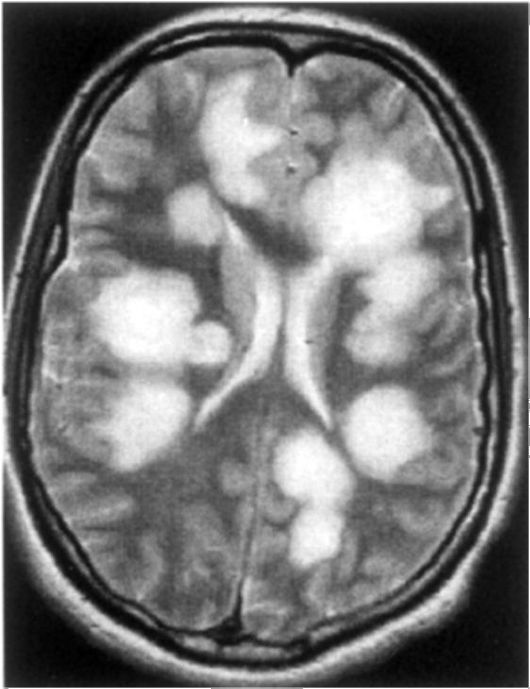

Демиелинизирующие заболевания мозга: МРТ изображения